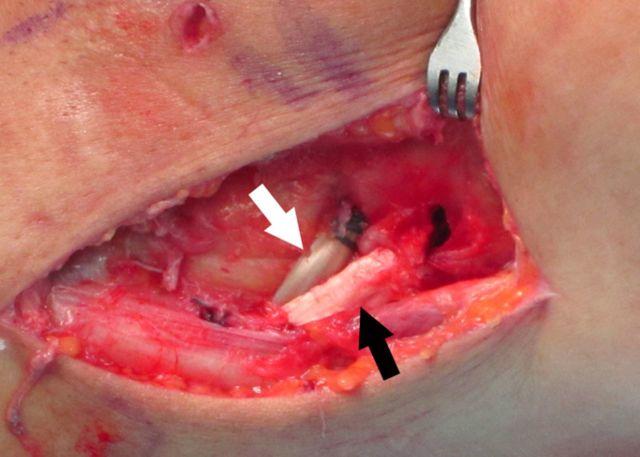

STEP 4 MAKE THE SKIN INCISION AND DEVELOP THE SURGICAL PLANE FOR THE POSTEROLATERAL CORNER RECONSTRUCTION: Create a 7-mm fibular tunnel in a counterclockwise direction to avoid breaking the lateral cortex of the fibular tunnel or injuring the peroneal nerve.

步骤4 做皮肤切口并为后外侧角重建开辟手术平面:沿逆时针方向创建一个7毫米的腓骨隧道,以避免破坏腓骨隧道的外侧皮质或损伤腓总神经。